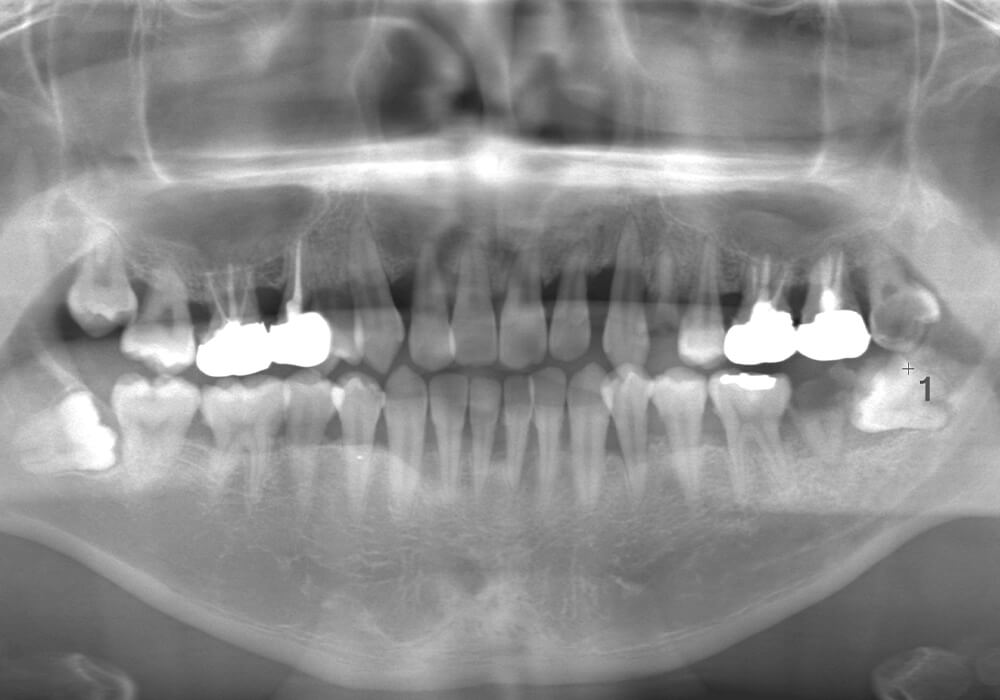

CASE 10

基本情報

| 年齢・性別 | 39歳・男性 |

|---|---|

| 主訴 | 左上下親知らず抜きたい |

| 抜歯期間 | 30分 |

| 抜歯費用 | 約2,500円(保険内) 別途CT撮影で3,000円 (2022年7月現在) |

| 抜歯内容 | 左上下の親知らず抜歯 |

| 治療方針 |

親知らずは抜いたほうが良い認識はあったものの、痛みや腫れが出ることを知って、勇気が出ないままでいたとのことでした。 そのまま放置していたら虫歯になってしまい、今回ご来院されました。しっかりと麻酔をして緊張をほぐしながら抜歯を始めました。完全萌出のため、時間を要することなくすぐに抜歯することができました。 |